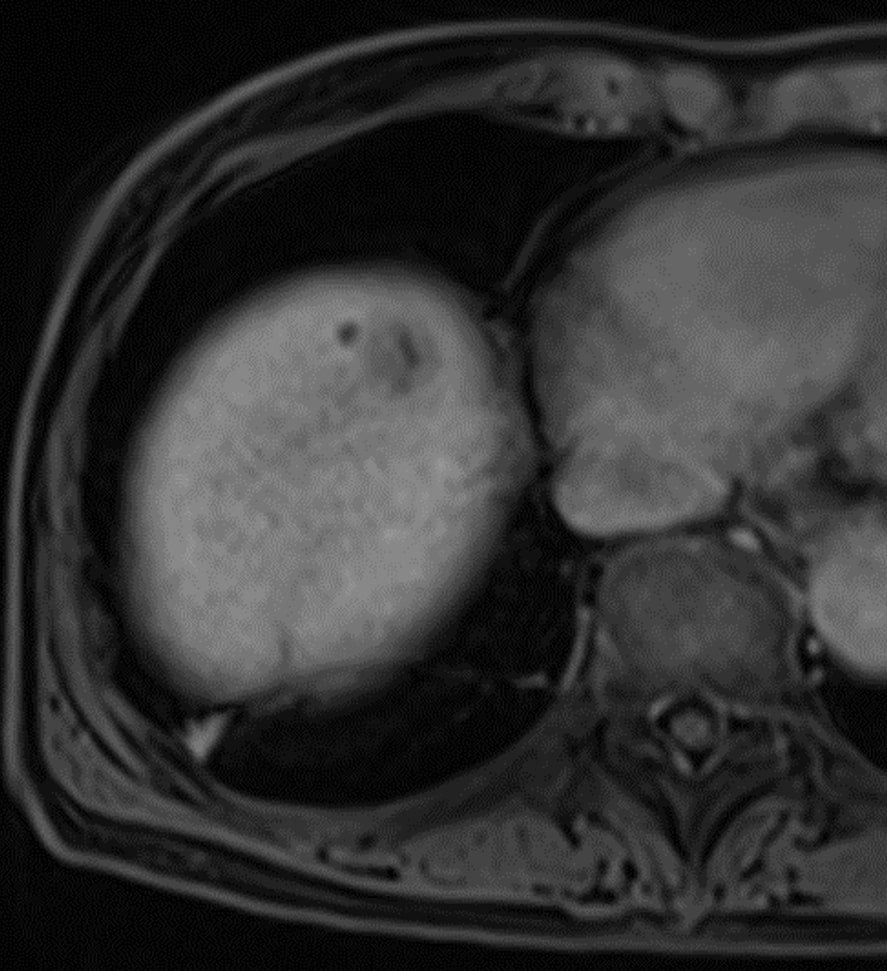

60歳代、女性、53kg、HCC

C型肝炎でフォロー中に肝腫瘍の指摘あり。前医CTにて肝内胆管癌が疑われ、手術目的に当院紹介。肝腫瘍の術前精査目的に再度造影CTとEOB-MRIを施行した。

Necrotic HCCと診断され、切除術を施行された。病理診断でも No residual carcinoma with necrosisとの診断であった。その後再発を認めず、経過観察となっている。

C型肝炎でフォロー中に出現した肝腫瘤について、前医CTではiCCが疑われたが、EOB-MRIにてNecrotic HCCが疑われた。肝切除を施行し、病理学的にもNecrotic HCCが証明された。EOB-MRIは,肝腫瘍の質的診断において有用であることが、あらためて確認された。